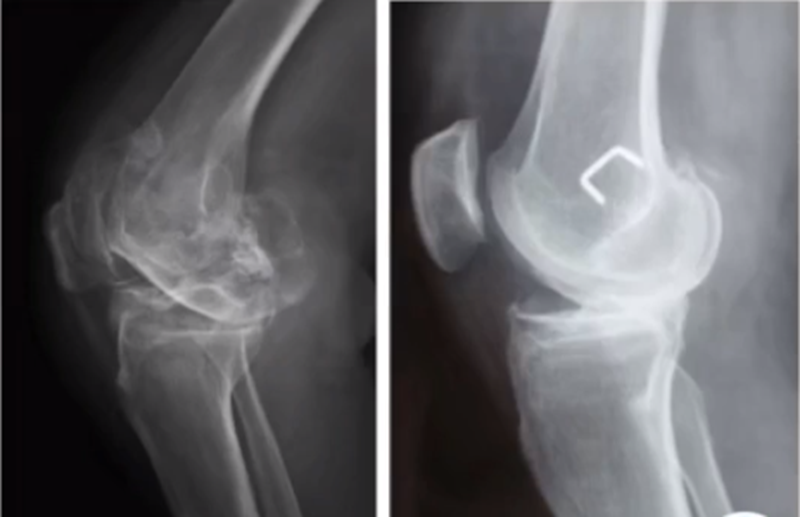

三、单髁置换的适应证——标准侧位片

标准侧位片,内外髁完全重叠,胫骨平台也一样,如果检查不标准,X线片结果会影响判断。

侧位片可以显示胫骨平台磨损部位,在判断前交叉韧带功能是否完好方面有重要意义。当磨损部位在前方或中前方,没有延伸到胫骨平台后缘时,说明前交叉韧带功能正常;当磨损部位延伸到胫骨平台后方,甚至引起后方半脱位状态时,说明前交叉韧带功能缺失或损害,此时不适合做单髁。

ACL功能完好是单髁重要的适应证。当ACL失去功能,导致后方软骨磨损或者骨缺损,此时为整个内侧或全间室的骨关节炎,不是单髁的适应证了。

在牛津单髁标准教程里,表明前交叉韧带与后交叉韧带都应该保持功能正常,才是单髁的适应证。